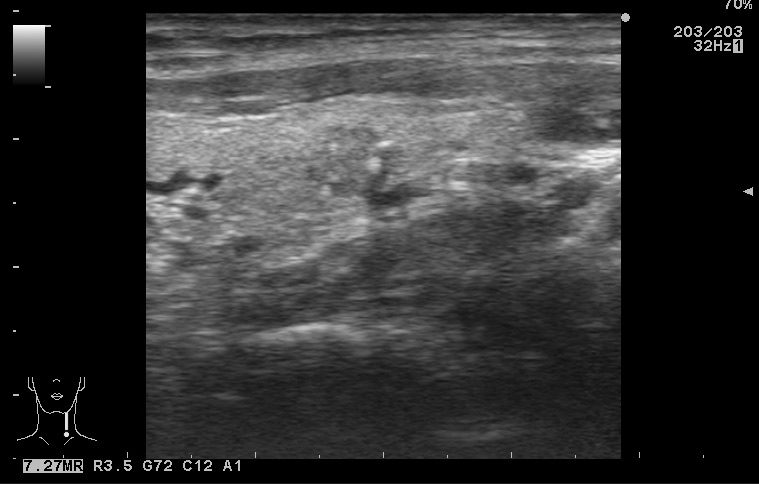

Папиллярная карцинома, УЗИ

Мужчина средних лет.

изоэхогенный узел с кальцинатами

Типичная картина, кстати.

Папилляная карцинома.

Диагноз доказан морфологически (ТАБ, гистология).